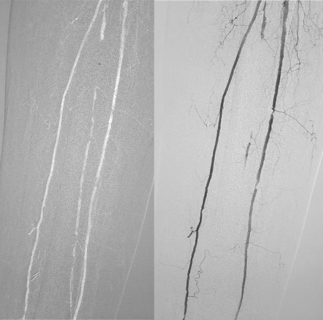

Our goal is simple: to make safer imaging the global standard of care. Through advanced CO2 delivery systems and continuous research collaboration, we support clinical decision-making where iodinated contrast agents carry unnecessary risk.